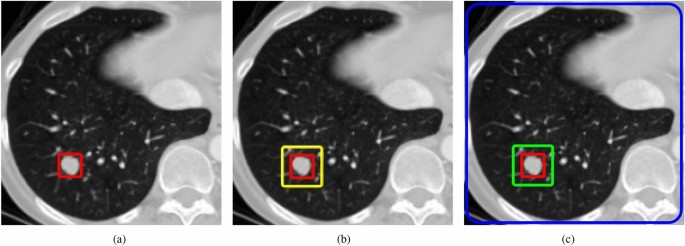

The downsampling module in RT-DETR employs computationally efficient 3\(\times\)3 convolutional blocks, which effectively reduce the number of model parameters and improve computational efficiency while maintaining a certain level of detection accuracy. However, its performance in lung nodule detection tasks remains suboptimal (details in Table 5). To address this, the Joint Context Feature (JCF) module is introduced to enhance the network’s downsampling capabilities. We designed the JCF module to mimic the human visual system by leveraging surrounding contextual information to enhance detection. As illustrated in Fig. 4a, if the human visual system tries to locate the red region by focusing solely on the target itself, it becomes challenging because the target occupies only a small portion of the overall area. In Fig. 4b, defining the white region as the surrounding environment of the red box and utilizing information from the white box makes it easier to detect the target. For Fig. 4c, incorporating information from the entire scene (green box) in conjunction with the red and white regions further reduces the difficulty of target detection.

The illustration of target detection by leveraging surrounding contextual information. The JCF module mimics the human visual system by leveraging surrounding contextual information to enhance detection.